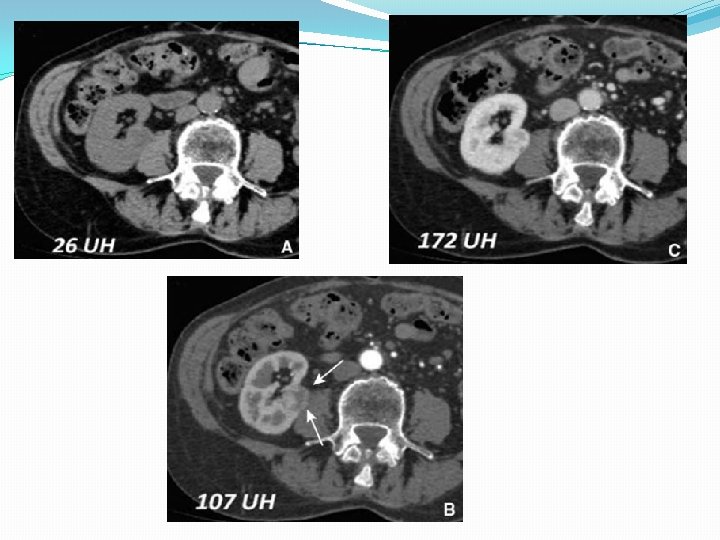

Examen tomodensitométrique - Examen de référence - détection et la caractérisation de la tumeur - bilan d’extension locorégional. La sensibilité : 90 % La TDM est fiable pour la détection des lésions de taille inférieure ou égale à 1 cm,

Le passage sans injection La phase artérielle ; cartographie artérielle rénale et tumorale La phase corticomédullaire apporte l’élément clé de la caractérisation tumorale qu’est le rehaussement significatif au-delà de 12 UH La phase parenchymateuse ou néphrographique plus sensible dans la détection des petites lésions hypodenses. La phase excrétoire